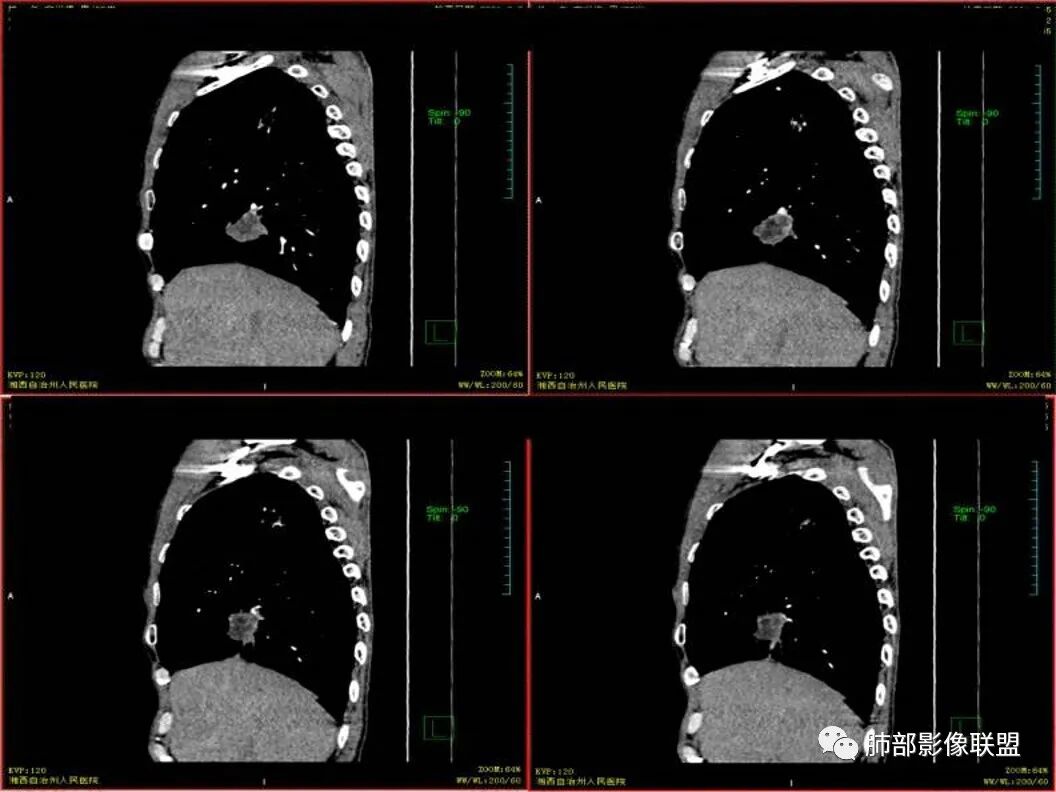

双上肺多发病灶,考虑结核(陈旧灶为主),右肺下叶前基底段占位,分叶、毛刺、胸膜牵拉,中央坏死,局部壁不光滑,前基底段支气管未见显示,不均匀强化,病灶远端阻塞性炎症,纵隔淋巴结肿大、融合。综合考虑恶性病变,鳞癌可能大。

临床 中年男性,咳嗽盗汗、老结核史,血沉高、t试验阳性,结核应该存在,cyf高4倍,价值怎么样待验证。影像 :两上肺实变加粗大索条灶,两肺野弥漫粟粒,考虑结核应该问题不大。重点分析右下病灶:隆突下淋巴结肿大,但伴钙化,有边缘强化?淋巴结融合又是恶性征像?右下肺病灶冠状位总体方正,横断位总体三角型,长毛刺、近端也有渗出、坏死彻底、空洞壁光滑锐利,似有边缘强化?看做薄壁空洞?以上符合炎性病灶。   支持恶性的征像 :冠状位的空洞似有壁结节,偏心坏死。   综合 ,右下肺鳞癌(偏心空洞+cfy)+两肺结核。

老年男性,既往有肺结核病史。影像双上肺病灶考虑陈旧性肺结核病灶,关键是右下肺团块影,从视频看,右下叶前段分支有堵塞,病灶局部膨隆,有分叶,周围有磨玻璃,但边界不大清楚,远端还有可以阻塞性炎征象,内部有偏远心端坏死,故考虑恶性可能性大。

影像表现为 双肺上叶多发索条斑片影,可见支气管牵拉性扩张,考虑为陈旧肺结核纤维硬结灶。右肺下叶前基底段团块影膨隆生长,边界不清,呈分叶,毛刺,胸膜牵拉,支气管截断,中央区坏死明显,但未形成空洞,坏死区边缘光整,不均匀环形强化,隐约见壁结节。纵隔淋巴结肿大伴钙化,病灶远端见阻塞性炎症,结合CYFRA21-1偏高,应想到考虑恶性病变,鳞癌可能性大。